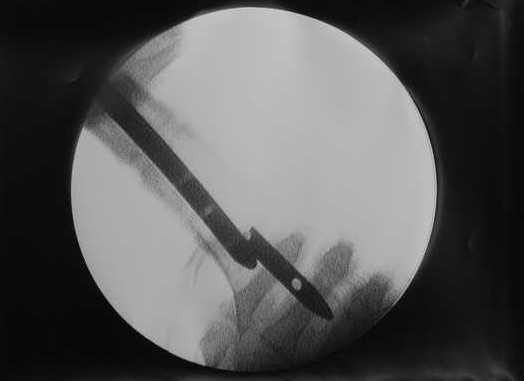

27 марта выполнено удаление блокирующих винтов (сломанный винт пришлось высверливать цапфен-бором), сломанного штифта (дистальный фрагмент удален через канал, образованный разверткой из коленного сустава - image 4),

В приложении пример, дистальный отломок пружинил кзади. Два винта потому, что первый оказался чуть кпереди и не упирался в гвоздь.